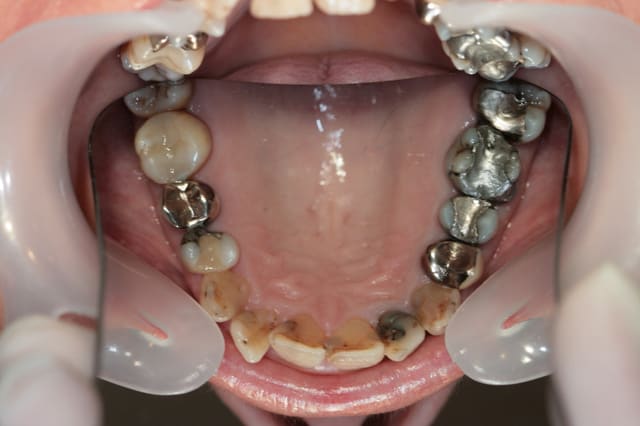

Récemment Céramik râlé, parce qu'il n'y avait pas de nouveau cas (esthétique je crois) à se mettre sous la dent. Je me jettes à l'eau avec ce dernier cas posé ce vendredi (y'a pas plus frais), une larme à l'oeil parce qu'il s'agit aussi du dernier gros cas dans mon cabinet que je quitte cette semaine pour rejoindre ma belle et nos p'tits bouts loin la bas dans le sud.

La patiente a un sourire très médiocre avec migration de plus en plus marqué du bloc incisivocanin sup. Comment l'aidez vous?